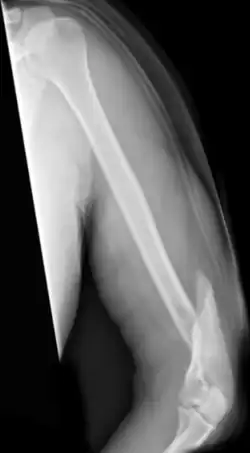

Spiralförmige Humerusschaftfraktur

Als Humerusfraktur werden Brüche des Oberarmknochens bezeichnet.